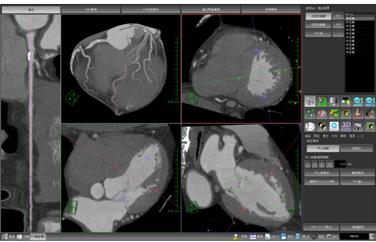

肝臓には動脈,門脈,静脈などの血管系が存在し,複雑に走行しています。その内部の血管走行をあらかじめ知っておくことは,肝切除術の術前情報として非常に重要です。肝臓解析ソフトウェアでは,新しいレンダリング技術を採り入れることにより,肝臓内部の血管走行を明瞭に表現することを可能にしました(図5)。さらに,血管支配領域をシミュレートした際の境界面にMPRを表示させることも可能です(図6)。それぞれの血管の位置関係や距離,腫瘍付近の血管の詳細情報,および対象物の肝臓表面からの位置関係などを明瞭に表現することができます。

![]() 図5 肝臓解析ソフトウェア 新しいレンダリング法を用いることで肝臓内の血管走行を明確に表示します。 |